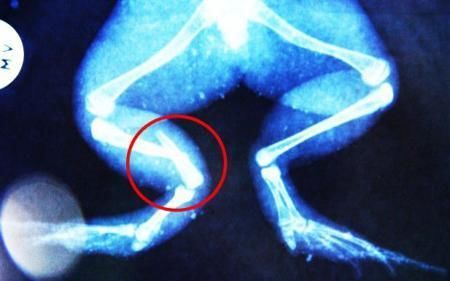

環(huán)球網(wǎng)4月2日報道 據(jù)《每日郵報》報道,上個月,南非大牛蛙布魯萊的右小腿被鄰居家的一只狗咬到,導致粉碎性骨折,現(xiàn)在經(jīng)過2個小時的手術,它的斷腿已經(jīng)被接上,它也因此成為有史以來第一只通過外科手術用鋼針接上斷腿的青蛙。

布魯萊的主人,居住在南非約翰內(nèi)斯堡附近的62歲的安妮·米恩斯說:“我對這只青蛙如此關心,人們一定認為我瘋了,但是我無法眼睜睜看著它那么痛苦。青蛙因其靈活的腿腳而著稱,一想到布魯萊的腿里要留下一個薄金屬片,我就感到心痛。然而我知道,如果不進行手術,布魯萊以后就沒辦法動彈了。因此我匆匆趕到獸醫(yī)那里,央求他給這只可憐的青蛙動手術。這位獸醫(yī)整天救助小貓小狗,他很難理解為什么我這么擔心一只青蛙,但是最終他還是答應了給布魯萊做手術。手術后是幾個小時的焦急等待,我們希望它能快快蘇醒過來。不過現(xiàn)在它的傷口已經(jīng)愈合,又能在花園里跳來跳去了。X光照射顯示,它會恢復的跟以前一樣。”

野生生物專家安妮經(jīng)常為學校寫教材,她認為這是人類第一次通過手術給一只青蛙接斷腿。在手術開始階段,獸醫(yī)把少量給狗用的麻醉藥注入到這只青蛙體內(nèi),讓它失去知覺。然后他在布魯萊的斷腿上切開一個小口,把一根小鋼針植入腿里。最后獸醫(yī)給它縫了9針,把切口縫合在一起。僅僅幾周后,布魯萊就能在安妮家附近活動了。這只青蛙大約已有25歲,主要以嚙齒動物、蛇和其他青蛙為食。布魯萊所屬的牛蛙種群正在不斷減小,目前只能在非洲南部的濕地里才能看到這種青蛙。